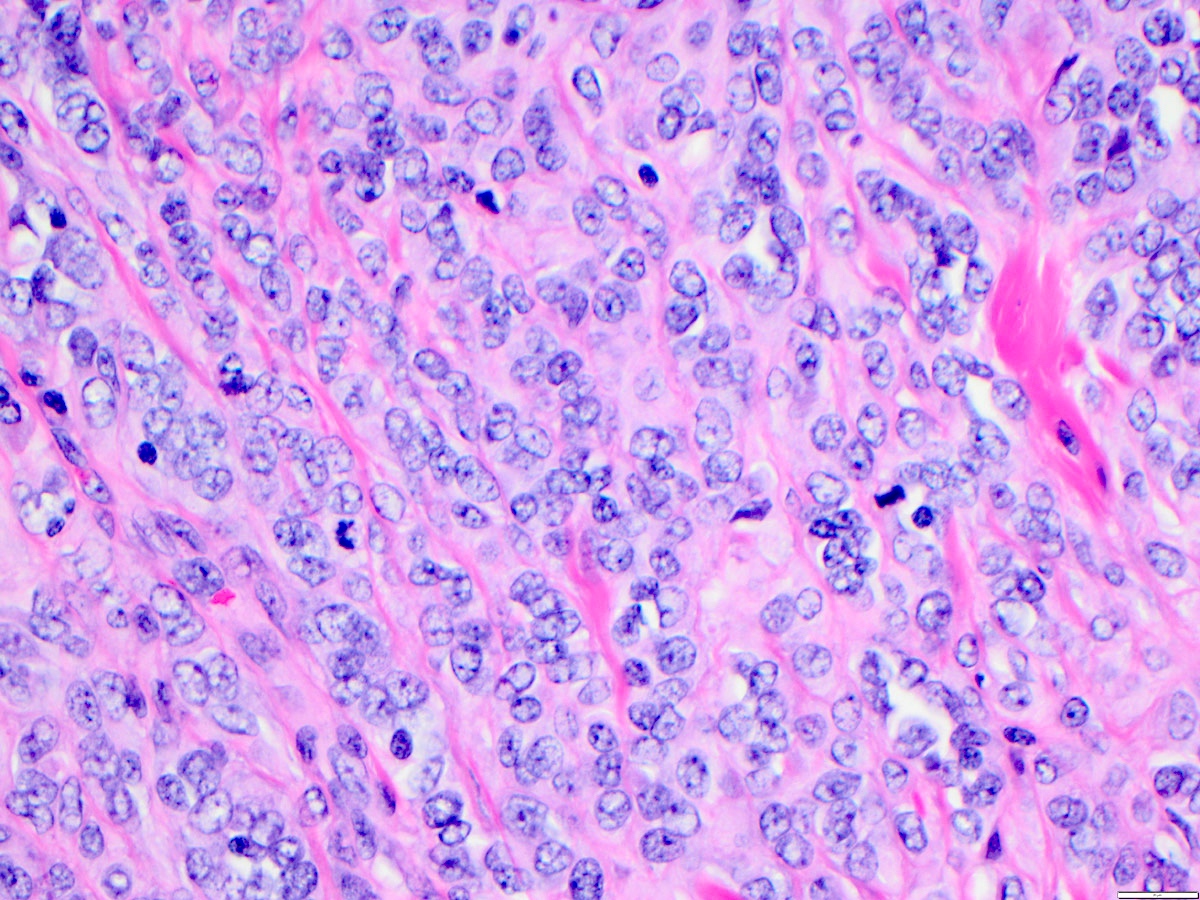

Microscopic (histologic) description

• Angiosarcoma has a wide morphologic appearance, ranging from lesions that are cytologically bland and vasoformative, to solid sheets of highly pleomorphic cells without definitive vasoformation

• Numerous irregularly shaped anastomosing vascular channels lined by atypical endothelial cells with a highly infiltrative architecture and poor demarcation

• Tumor cells are typically plump, pleomorphic and mitotically active

• They can be spindle shaped, polygonal, epithelioid and primitive round cells, forming papillae or solid nests within vascular lumina

• Tumor vessels ramify the dermis and intercalate through dermal collagen and subcutaneous soft tissues

• Because of the heterogeneous histologic features in poorly differentiated tumors, the histological identification of an angiosarcoma can be challenging

• Solid growth pattern often presents in poorly differentiated angiosarcoma

• Intratumoral hemorrhage is common

• Stromal lymphoid aggregates may also be present

Solid pattern of angiosarcoma